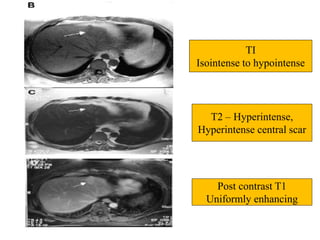

TI

Isointense to hypointense

T2 – Hyperintense,

Hyperintense central scar

Post contrast T1

Uniformly enhancing